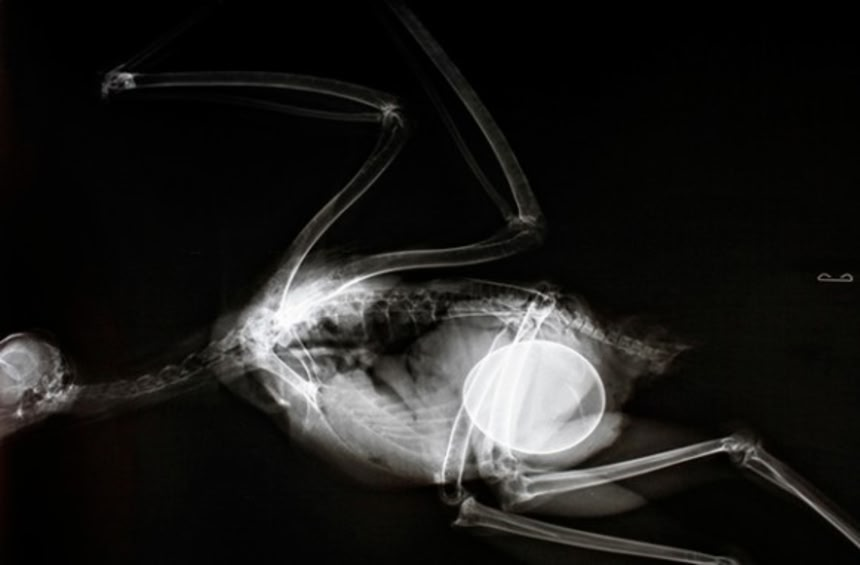

この画像を大きなサイズで見る10. アカオノスリ (鳥)

キーウィの中にキウィ入ってる・・・

キーウィさんに至ってはもう何も言うまいってレベル。命賭し過ぎ…

キーウィーの卵……母体のどこよりも大きい卵を産むんだね…